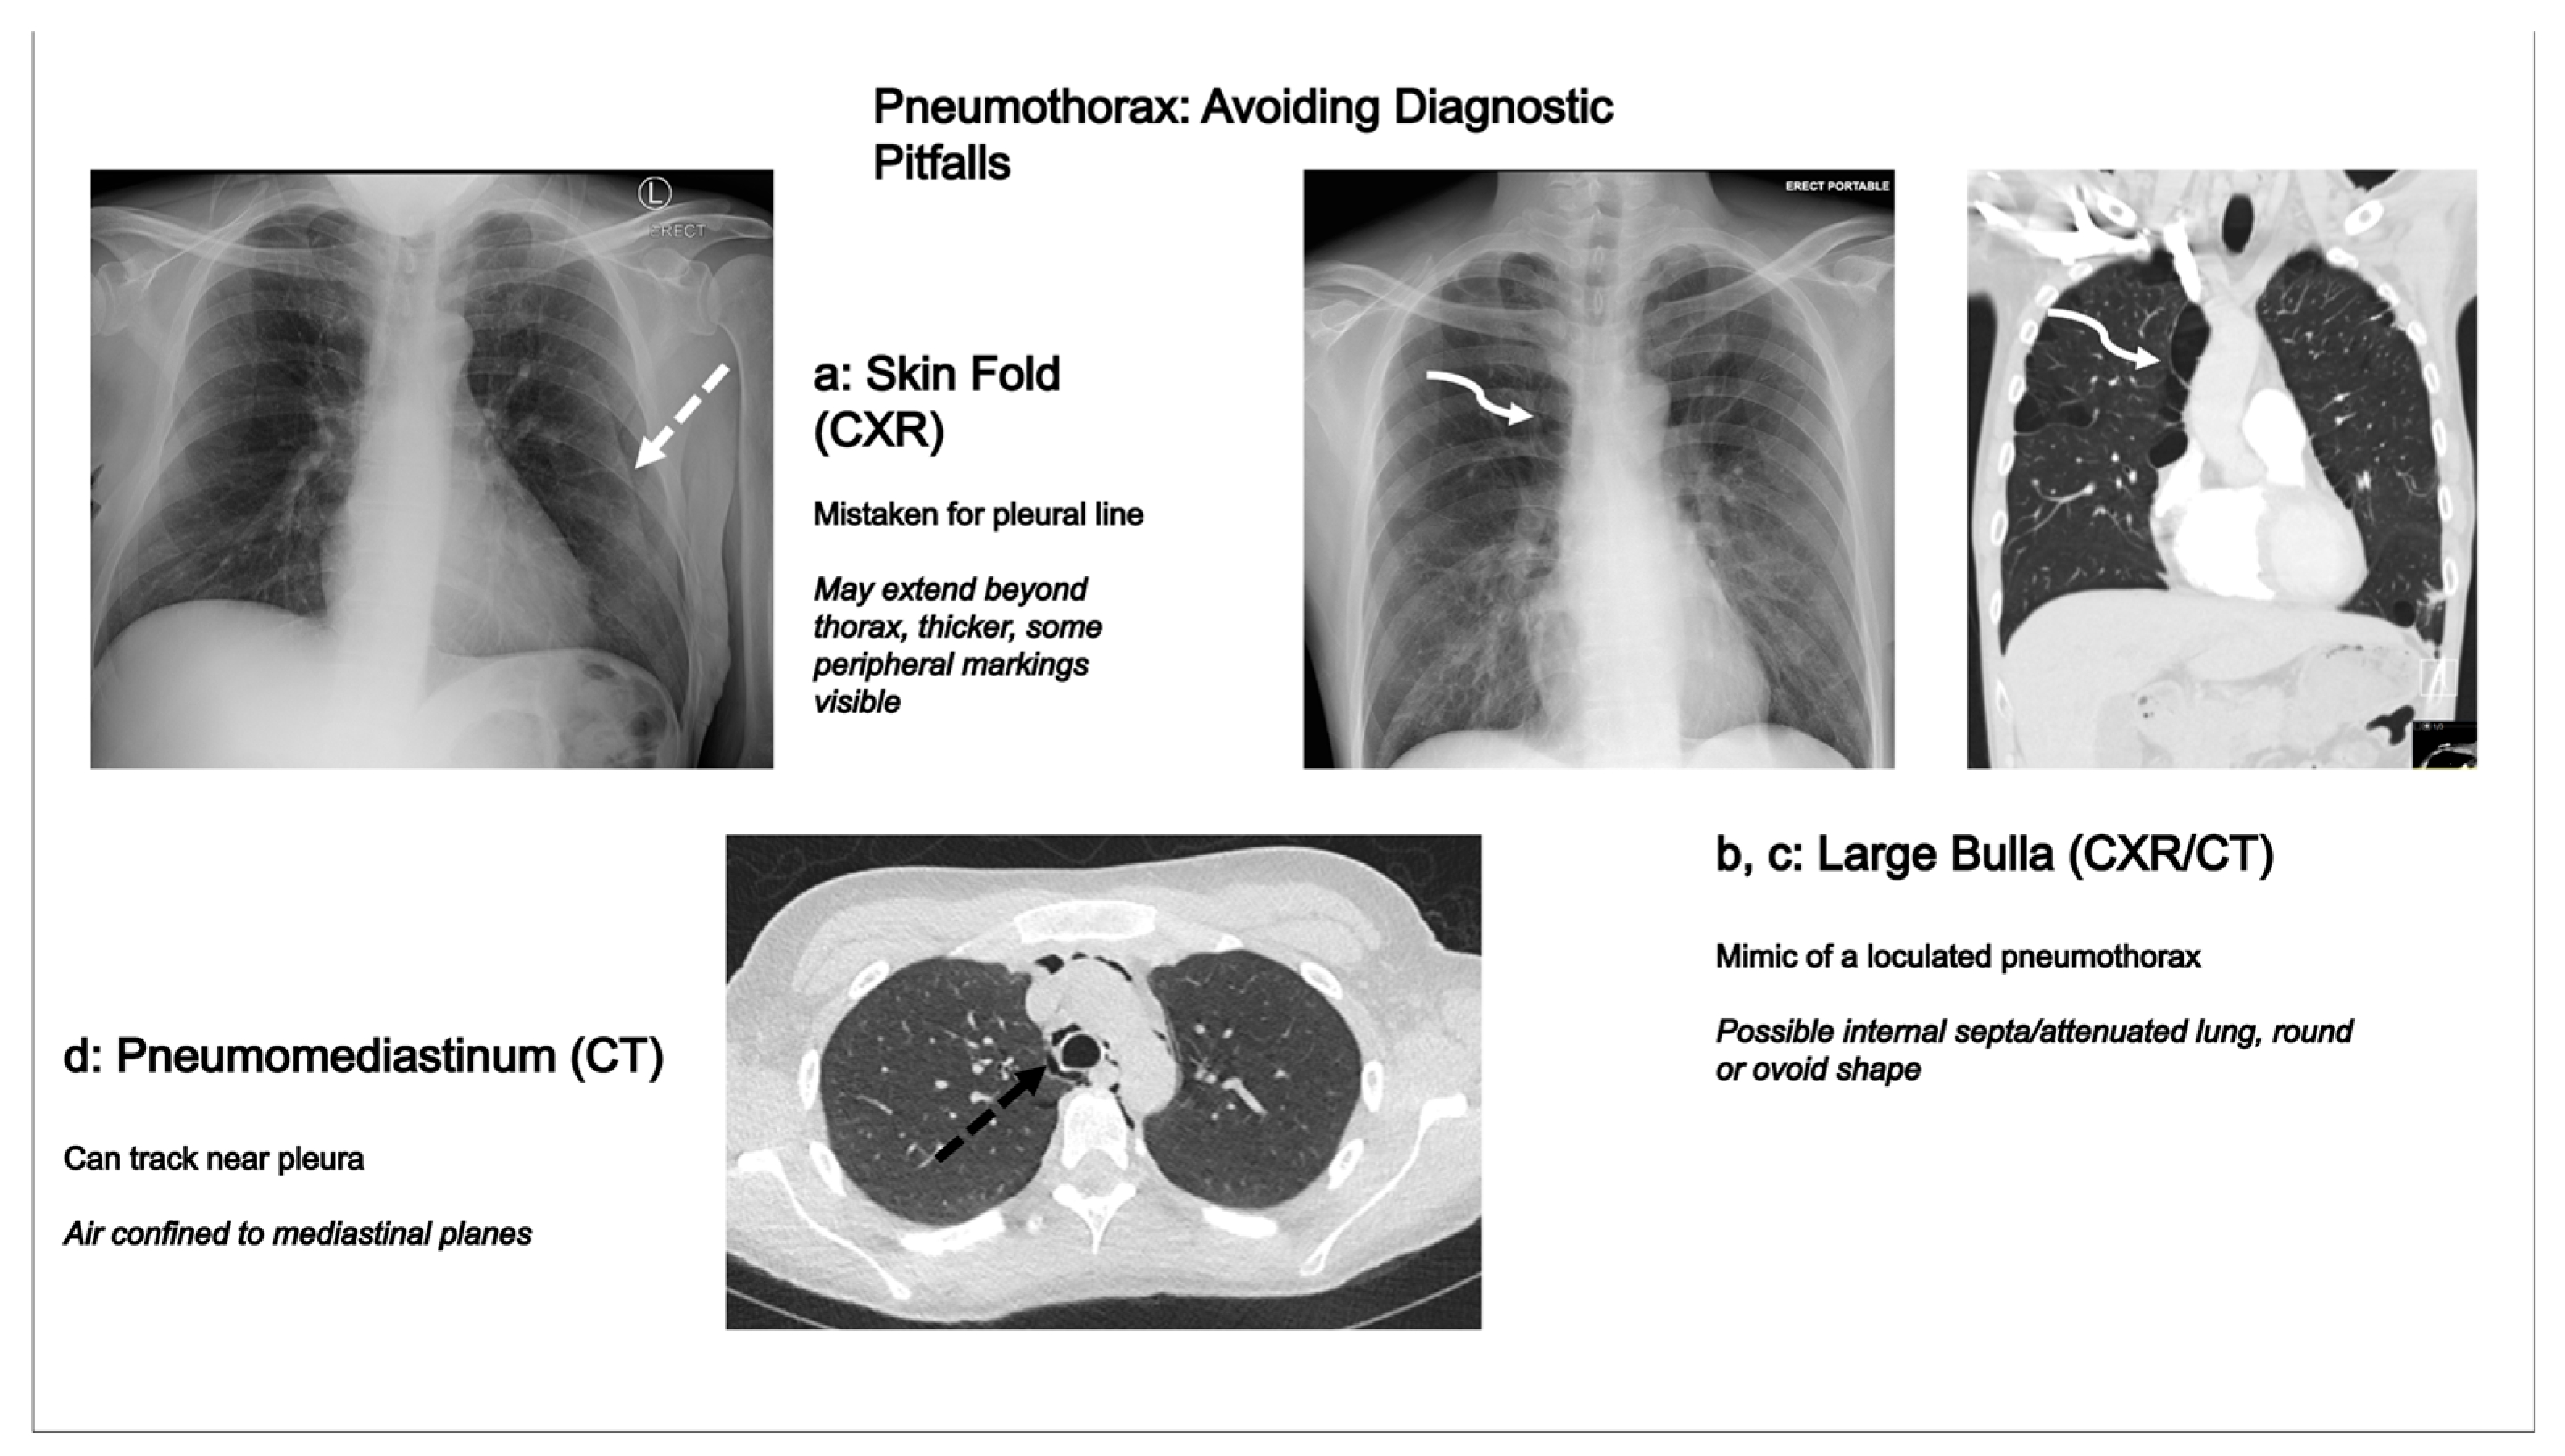

4.1. Chest Radiography Pitfalls

4.2. Computed Tomography Pitfalls